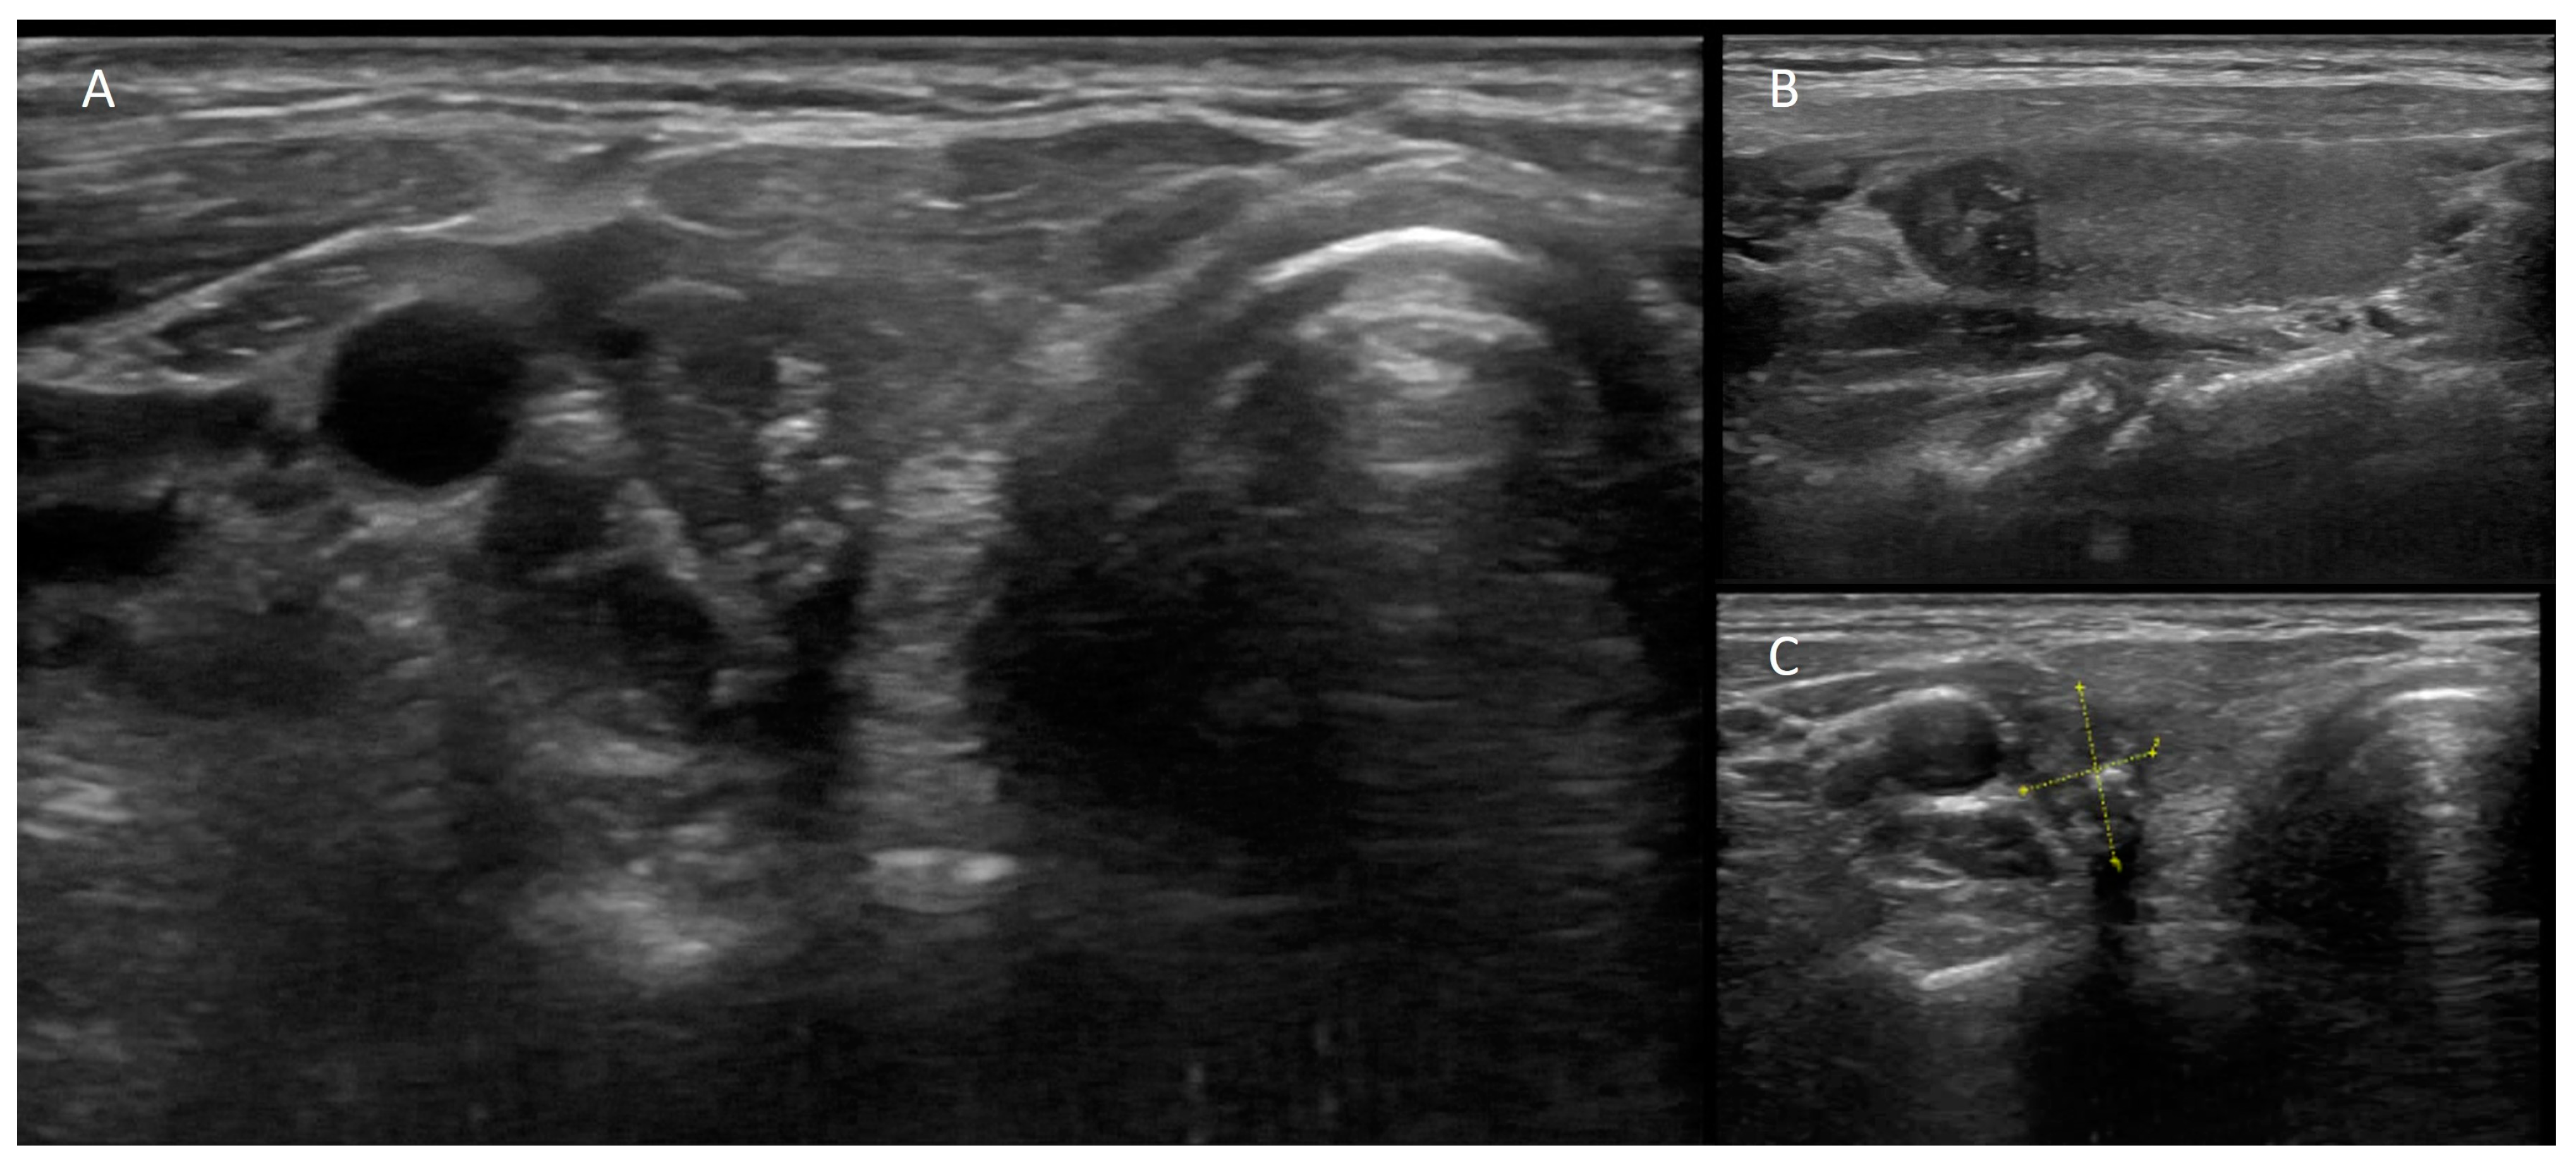

- Giovanella, L.; Campenni, A.; Treglia, G.; Verburg, F.A.; Trimboli, P.; Ceriani, L.; Bongiovanni, M. Molecular Imaging with (99m)Tc-MIBI and Molecular Testing for Mutations in Differentiating Benign from Malignant Follicular Neoplasm: A Prospective Comparison. Eur. J. Nucl. Med. Mol. Imaging 2016, 43, 1018–1026. [Google Scholar] [CrossRef]

- Campennì, A.; Giovanella, L.; Siracusa, M.; Alibrandi, A.; Pignata, S.A.; Giovinazzo, S.; Trimarchi, F.; Ruggeri, R.M.; Baldari, S. (99m)Tc-Methoxy-Isobutyl-Isonitrile Scintigraphy Is a Useful Tool for Assessing the Risk of Malignancy in Thyroid Nodules with Indeterminate Fine-Needle Cytology. Thyroid 2016, 26, 1101–1109. [Google Scholar] [CrossRef]

- Campennì, A.; Siracusa, M.; Ruggeri, R.M.; Laudicella, R.; Pignata, S.A.; Baldari, S.; Giovanella, L. Differentiating Malignant from Benign Thyroid Nodules with Indeterminate Cytology by 99m Tc-MIBI Scan: A New Quantitative Method for Improving Diagnostic Accuracy. Sci. Rep. 2017, 7, 6147. [Google Scholar] [CrossRef]

- Schenke, S.A.; Campennì, A.; Tuncel, M.; Bottoni, G.; Sager, S.; Crncic, T.B.; Rozic, D.; Görges, R.; Özcan, P.P.; Groener, D.; et al. Diagnostic Performance of 99mTc-Methoxy-Isobuty-Isonitrile (MIBI) for Risk Stratification of Hypofunctioning Thyroid Nodules: A European Multicenter Study. Diagnostics 2022, 12, 1358. [Google Scholar] [CrossRef]